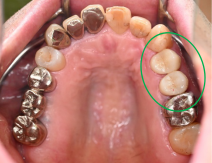

女性 Aさん 50代 (セラミックインレー)

主訴

左上の銀歯2本を白くしたい。

治療内容

銀歯を取り除き、セラミックインレーをいれました。

所感

患者さんは、お口の中の金属を徐々に取り除くことを希望され、今回は左上の奥歯2本をセラミックに替え、ノンメタルにしました。体全体の健康を考えると正しい選択だと思います。

セラミックインレー2本:¥52,800×2本=¥105,600(税込)